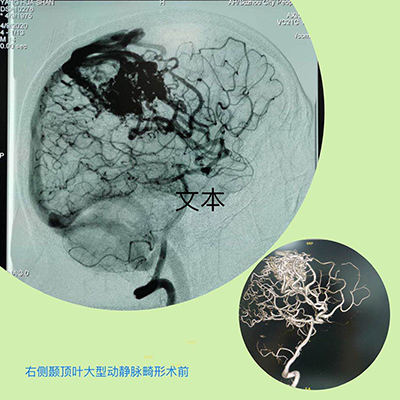

就在杨先生一家人感觉无望时,在一位病友的推荐下,找到了马修尧主任。在杨先生住院后的几天里,马修尧主任、任超、刘彬副主任,认真阅读了杨先生的外院检查CT、MRI和MRA等所有的影像资料,考虑是脑动静脉畸形,由于病灶巨大,直经接近7.0cm,且位于重要脑功能区,治疗上稍有不慎,便会导致肢体瘫痪甚至危及生命。马修尧主任认识到手术的高度风险,深感责任重大,带领团队积极查阅国内外相关文献,主动与省内外脑血管病知名专家深入交流,探讨治疗方案,并组织了由医务科、心血管内科、介入导管室等相关科室组成的专家治疗团队,组织多学科讨论,集思广益。经过严密细致的评估,最终为杨先生制定了最优的手术方案。

据马修尧主任介绍:脑动静脉畸形,是一种先天性的局部脑血管发生的变异。在病变部位,脑动脉和脑静脉之间缺乏毛细血管,导致动脉和静脉直接相通,形成动、静脉之间的短路。这些异常的结构,使血液直接从压力高的动脉系统,流入压力较低的静脉系统,导致血流供应在脑内分布不均匀,引起头痛、癫痫和颅内出血等情况。